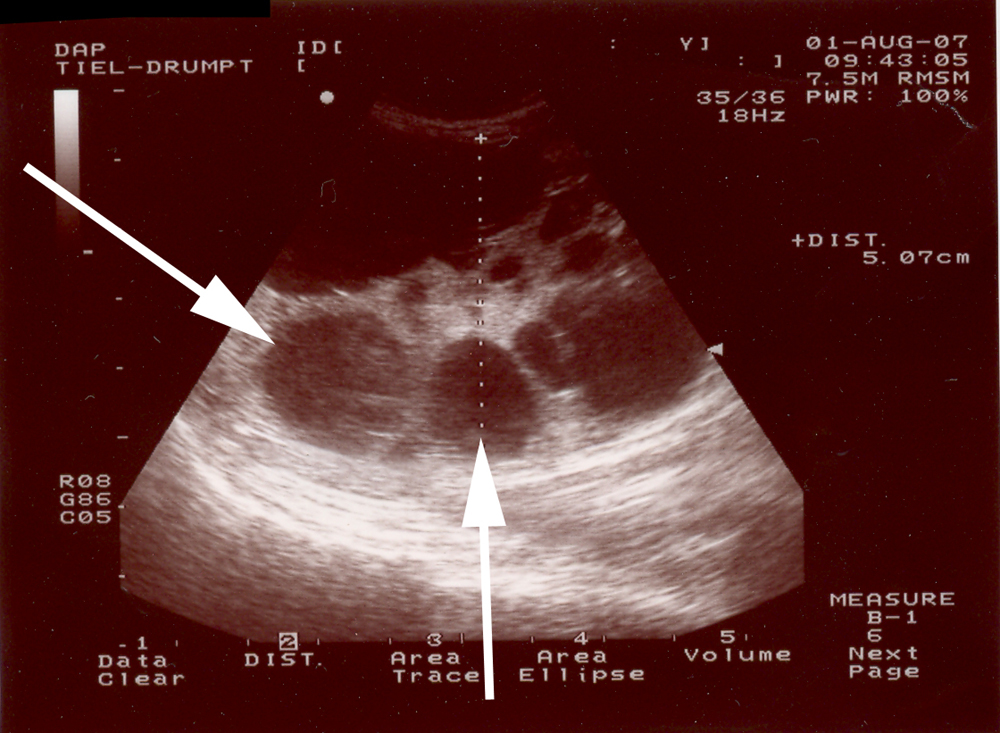

Er zijn meerdere cysten vanaf de geboorte in de beide nieren aanwezig. Ze komen zowel in het niermerg als in de nierschors voor. De cysten verdringen, terwijl ze groter worden, het normale nierweefsel.

Opvallend is dat er ook regelmatig laesies (= afwijkingen) in de lever worden gevonden bij katten met PKD.

Voor de preventie zijn alleen foktechnische maatregelen mogelijk. Hiervoor dien je te weten welke katten dragers zijn. Tot nu toe kon dat bekeken worden met de echo vanaf 4 weken leeftijd. Er konden helaas cysten gemist worden wanneer deze heel klein waren.